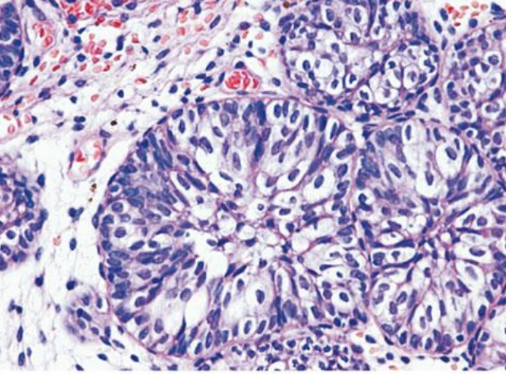

- Adenocarcinoma

- Ductal

- Acinar